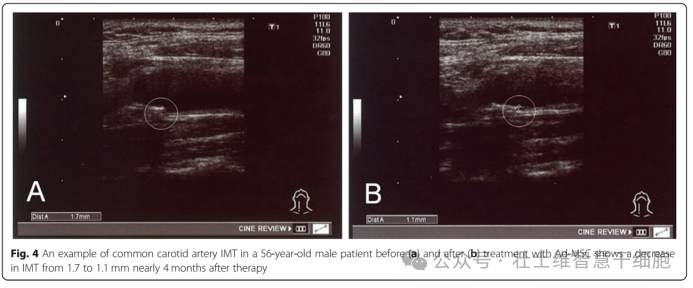

结果显示,患者治疗后高密度脂蛋白(HDL)、低密度脂蛋白(LDL)、残粒样微粒胆固醇水平显著改善,颈动脉内膜中层厚度(IMT)和心 - 踝血管指数(CAVI)均有明显优化,且所有患者未出现不良反应。其中一名 56 岁男性患者,治疗 4 个月后 IMT 从 1.7mm 降至 1.1mm;10 名处于疾病临界状态的患者,血脂相关检测指标也得到有效改善。